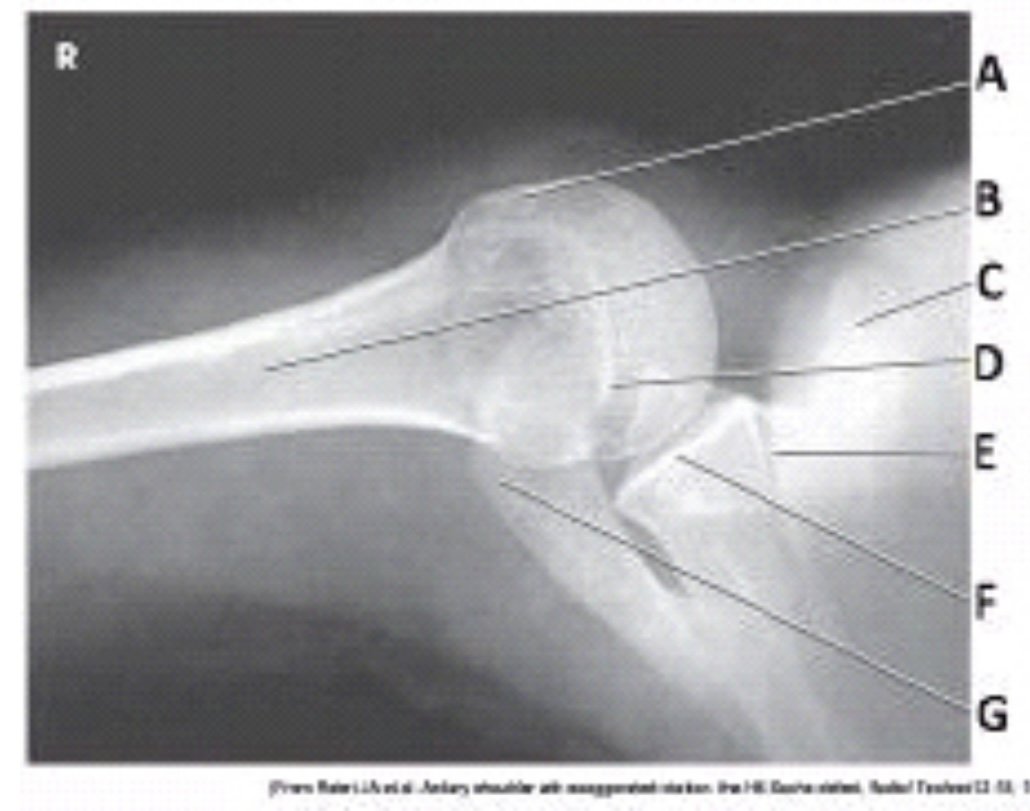

What projection (method) is demonstrated in the image below?

Inferosuperior axial (Lawrence)

What anatomy is labeled as letter A in the image below?

Lesser tubercle

What anatomy is labeled as letter C in the image below?

Coracoid process

What anatomy is labeled as letter D in the image below?

Acromion